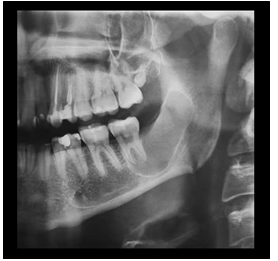

Se apreció en la ortopantomografía imagen pseudo radiolúcida localizada en el límite posterior del cuerpo mandibular, que se extendía desde las raíces de UD 37 hasta tercio medio de rama mandibular ipsilateral de bordes definidos, desplazando el conducto alveolar inferior y sin afectar la basal mandibular.

Figura 2 Detalle de Radiografía Panorámica que evidencia imagen pseudo radiolúcida unilocular de bordes corticalizados que se extiende en sentido cefálico caudal desde borde anterior de la rama y parte del reborde alveolar hasta la cortical del conducto mandibular izquierdo, se evidencia relación de la lesión con raíces de la UD 37. Fuente: Historia Clínica. Especialización Cirugía Bucal ULAC-IDOLA. 2022.